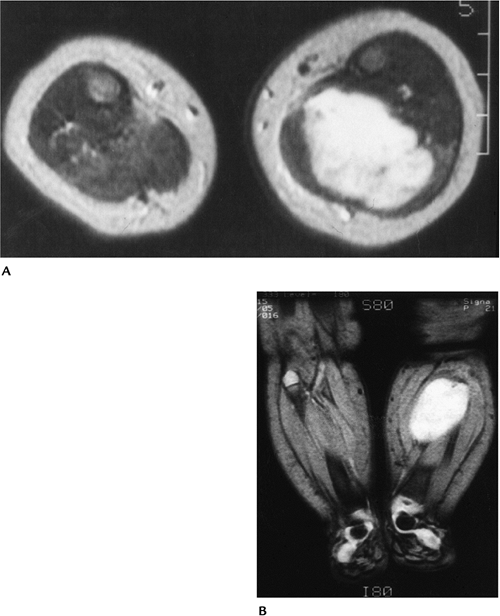

Suggested Reading

Weis SW, Goldblum JR. Enzinger and Weiss’s soft tissue tumors, 4th ed. St. Louis: Mosby; 2001:785–836.